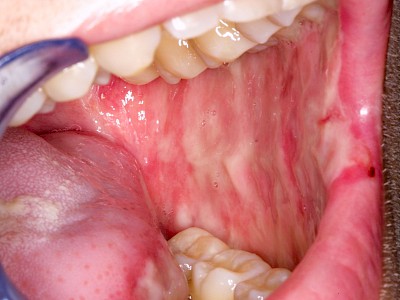

Kauen auf Wange, Zunge & Lippen

Das Kauen auf Wange, Zunge oder Lippen zählt zu den sogenannten Habits und ist meist stressbedingt. Diskrete Linien (Verhornungsleisten) oder aber unruhige Schleimhautareale bis hin zu Erscheinungsformen wie "wildes Fleisch" können dabei auffallen.

Beispiele32 Bilder